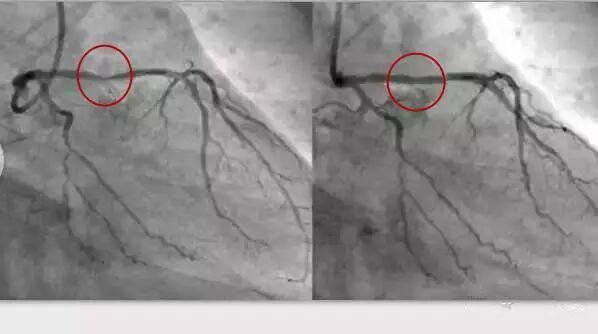

电脑截图,红色区域为狭窄的血管放入支架后变粗,使得血流正常通过。近年来,为了避免支架术后再次狭窄和梗阻,新一代的支架表面有一层药物涂层,大大减少了再次狭窄的发生率。